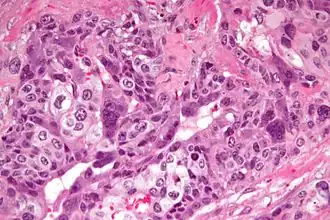

Хориокарциноматрофобластический рак, обычно плаценты. Он относится к злокачественному концу спектра при трофобластической болезни. Хориокарцинома также классифицируется как опухоль зародышевой клетки и может возникать в яичке или яичнике.